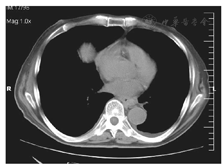

病例1尚某,男,69岁,退休干部,因晚期肝癌合并全身多发性转移,胸部CT示右侧胸腔大量积液入院,见图1。2014年12月16日入院时携带外院已行的"右侧胸腔引流管",每日控制引流胸水1 000 ml,生命征平稳,虚弱卧床,生活自理困难。入院后给予常规的支持治疗,于入院后第2日开始做胸腔三氧水灌注引流,每次注入100 ml,保留2 h后开放引流,每日2次。2 d后胸水开始明显减少,连续5 d。第5日以后24 h引流量仅有10 ml,CT检查报告为微量的积液,见图2。观察2 d无新生的胸水出现,于入院后第10日拔管,再两日患者好转出院。